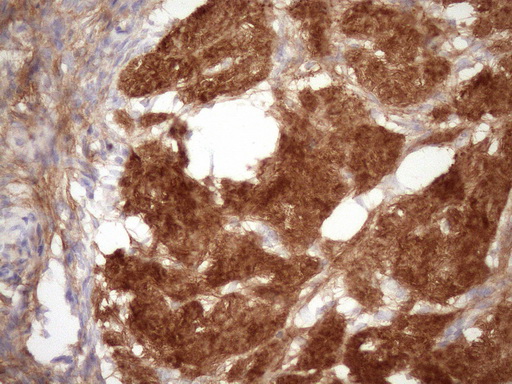

Expressed in the suprabasal region of the epidermis, in hair follicles, the basement membrane at the dermo- epidermal junction (occasionally extending into the basement membrane of dermal blood vessels), wounded skin and several invasive squamous cell carcinomas (at protein level). Expressed in normal and wounded skin and various squamous cell carcinomas.

Secreted, extracellular space. Cell membrane; Peripheral membrane protein. Extracellular and plasma membrane-associated. Colocalizes with HSPG2 in the pericellular environment of squamous cell carcinomas.